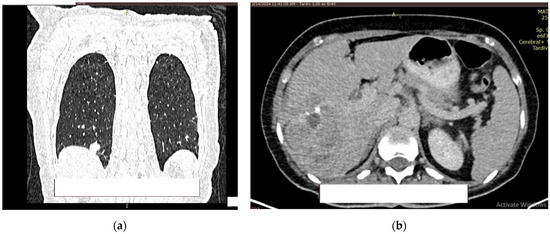

At 2 days postoperatively (post TURB), contrast CT was performed (creatinine values = 1.39 mg/dL) of the head, thorax, abdomen, and pelvis.

At the level of the pulmonary parenchyma, the CT examination showed multiple pulmonary nodules distributed diffusely and bilaterally with a metastases CT aspect, with the largest located in the posterobasal part of the right lung, with a 14 mm diameter (Figure 8a).

Figure 8.

Contrast CT aspect. If there are multiple panels, they should be listed as: (a) Description of what is contained in the first panel; (b) Description of what is contained in the second panel. Figures should be placed in the main text near to the first time they are cited.

No solid tumor masses were observed in the digestive tract; only intestinal fluid stasis and some hydroaeric levels were present. At the level of the right lobe of the liver, a poly nodular conglomerate with a 98/68 mm maximum diameter in the coronal plane, natively hypodense nodules, and postcontrast with the presence of metal clips from the previous liver surgery were visible (Figure 8b). It was unclear whether this finding represents a secondary liver lesion or is a result of the previous liver metastasectomy.